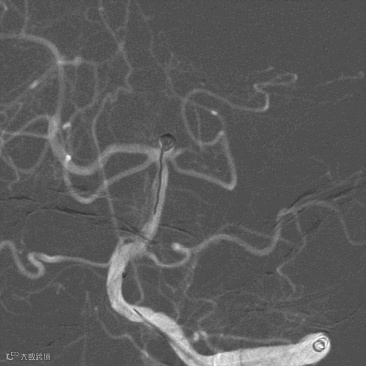

外院DSA示:基底动脉尖动脉瘤(图2 A,B)

图2